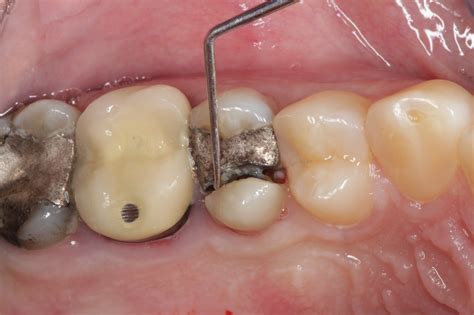

Cracked Tooth A crack runs from the chewing surface down toward the root. Usually needs a crown to prevent the crack from spreading.

Your dentist will use specialized imaging, such as X-rays or transillumination, to diagnose the extent of the crack in tooth. Based on their findings, they may recommend one of the following treatments:

• Root Canal Therapy: If the crack reaches the pulp (the inner nerve and blood vessel chamber) and causes infection or severe pain, a root canal is necessary to save the tooth and alleviate the symptoms.